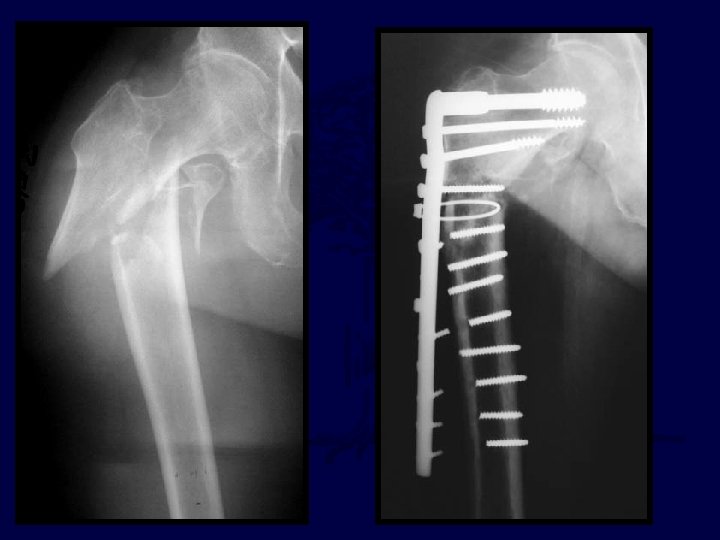

27 yo jogger struck by car, closed, isolated injury

27 yo jogger struck by car I’d reduce & fix with: A. 95° blade B. DCS plate C. “Recon” Nail D. DHS E. Intramedullary hip screw (PFN, TFN, IMHS, GAMMA)

A. The reduction is satisfactory B. The TAD is satisfactory C. Both are satisfactory D. Neither are satisfactory

* *

Progressive pain 11 -14 weeks (varus + plate is rarely good)

I’d Bonegraft & revise with: A. 95° blade B. DCS plate C. “Recon” Nail D. DHS E. IMHS F Other

95° DCS + auto. BG